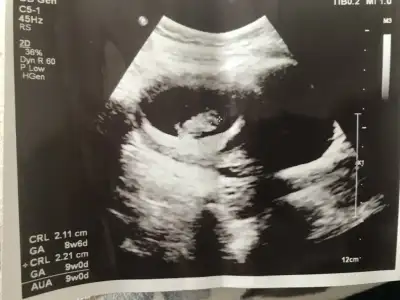

Canim yeni fotolarim geldi bakabilir misin bir Dr erkek dedi Kordon'da olabilir dedi..bugünde başka Dr gittim kıza benziyor dedi..kalp atışı olan fotoda solda bacakları nubu var yandan da baktı dr görebilmek için .sen ne düşünüyorsun 😊

Eklentiler

• IMG20210427113328.webp

IMG20210427113328.webp

18,4 KB · Görüntüleme: 50

• IMG20210427113336.webp

IMG20210427113336.webp

11,2 KB · Görüntüleme: 55

Emin olmadım ama kız sanki önceki usgde kız demiştim 🙈